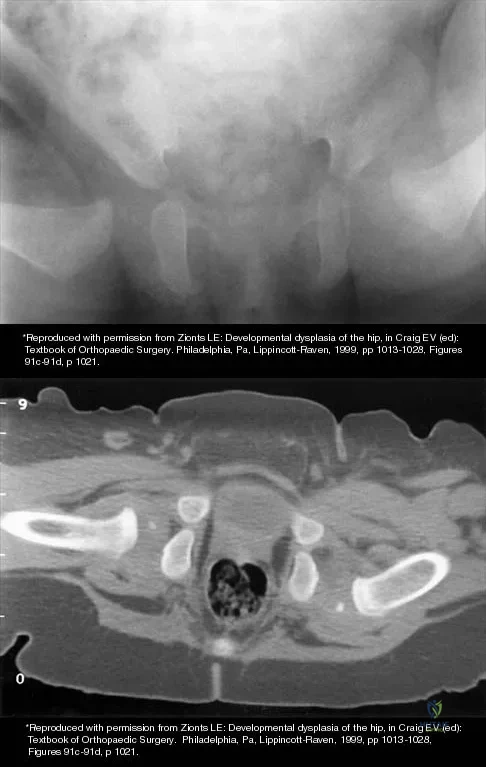

The mother of a 3-month-old infant states that she has difficulty positioning the infant's legs during diaper changes. Examination reveals limited abduction of both hips and a negative Ortolani sign. A radiograph reveals bilaterally dislocated hips. Initial management consists of guided reduction in a Pavlik harness, with weekly follow-up. Figures 57a and 57b show the radiograph and CT scan obtained after 6 weeks in the harness. Management should now consist of